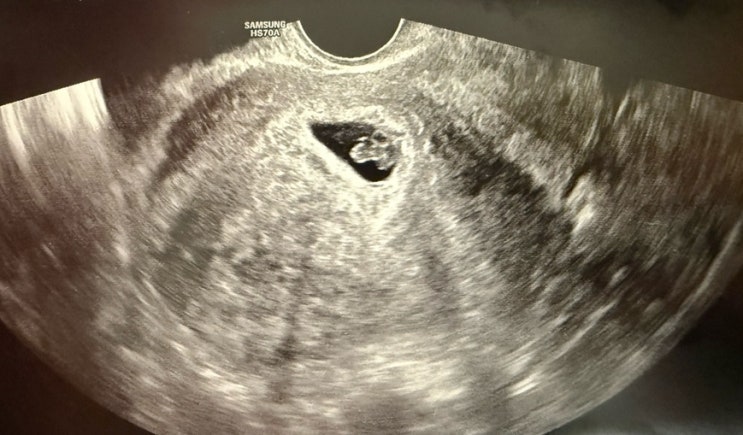

6주-7주 계류유산ㅠ 아기심장소리, 심박수 불안 결국 아기심정지…

피검 수치도 잘 나왔고 아기집 난황 심소 다 잘 보고 잘 들었지만 나는 왠지 계속 불안했다 ㅠㅠ 태몽도 없...